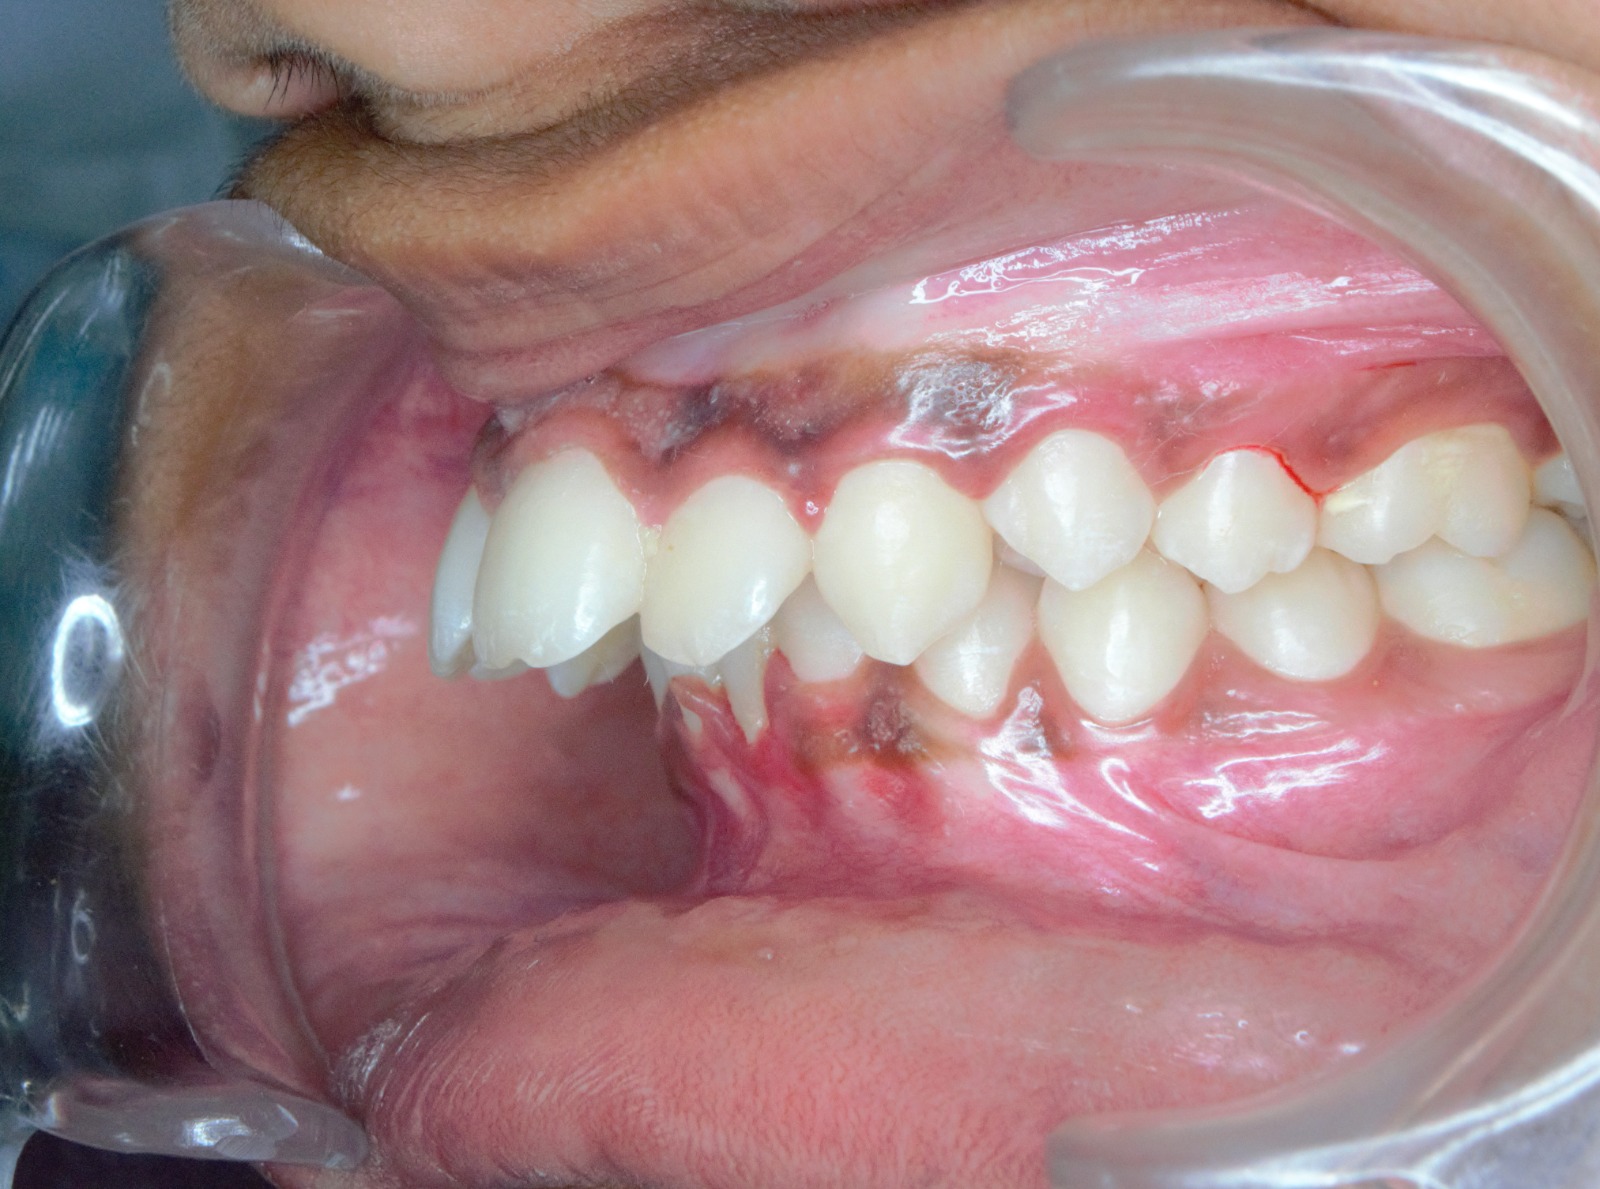

Sairam dental care located in Dharmapuri, with Leading Dentist In Oddapatti, is the Dental Hospital with exclusive root canal, Braces & Invisalign center. Led by renowned Drs Raghuraaman ( Periodontist) and Nivetha Raghuraaman ( Orthodontist) Sairam dental care offers gum treatment with expertise in laser, root canal treatment and digital smile correction with advanced technology aim to focus on aesthetics, comfort and precision. The clinic also specializes in Invisalign treatment, digital smile makeover, laser gum care, dental implants, root canal therapy, extractions and full-mouth rehabilitation blending compassionate care and clinical excellence.

Our professional, experienced, and passionate dentists make us the best choice for Invisalign treatment in Dharmapuri, providing top-notch dental services.